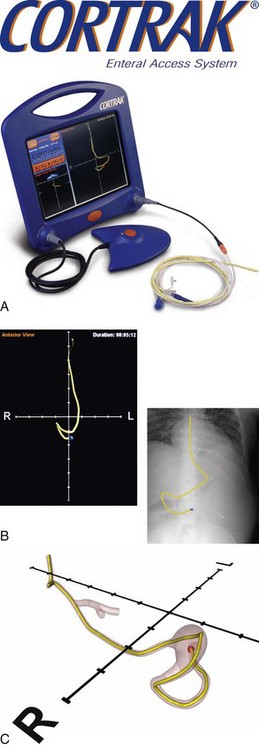

For those patients unable to tolerate gastric feedings who require relatively short-term nutrition support, a nasoduodenal tube (NDT) or a nasojejunal tube (NJT) is indicated. This requires that the tip of the tube pass through the pylorus and into the duodenum or pass all the way through the duodenum and into the jejunum. Positioning of these tubes requires one of the following techniques: (1) intraoperative placement (generally not just for the purpose of placing a feeding tube), (2) endoscopic or fluoroscopic guidance, (3) spontaneous placement that depends on a gastric tube migrating into the duodenum by peristalsis, or (4) bedside placement using a computer guidance system (Figure 14-3). Spontaneous migration of a gastric tube cannot be used for an NJT. Confirmation that the tube has migrated to the correct position can take several days and requires x-ray confirmation. This can result in delayed feedings